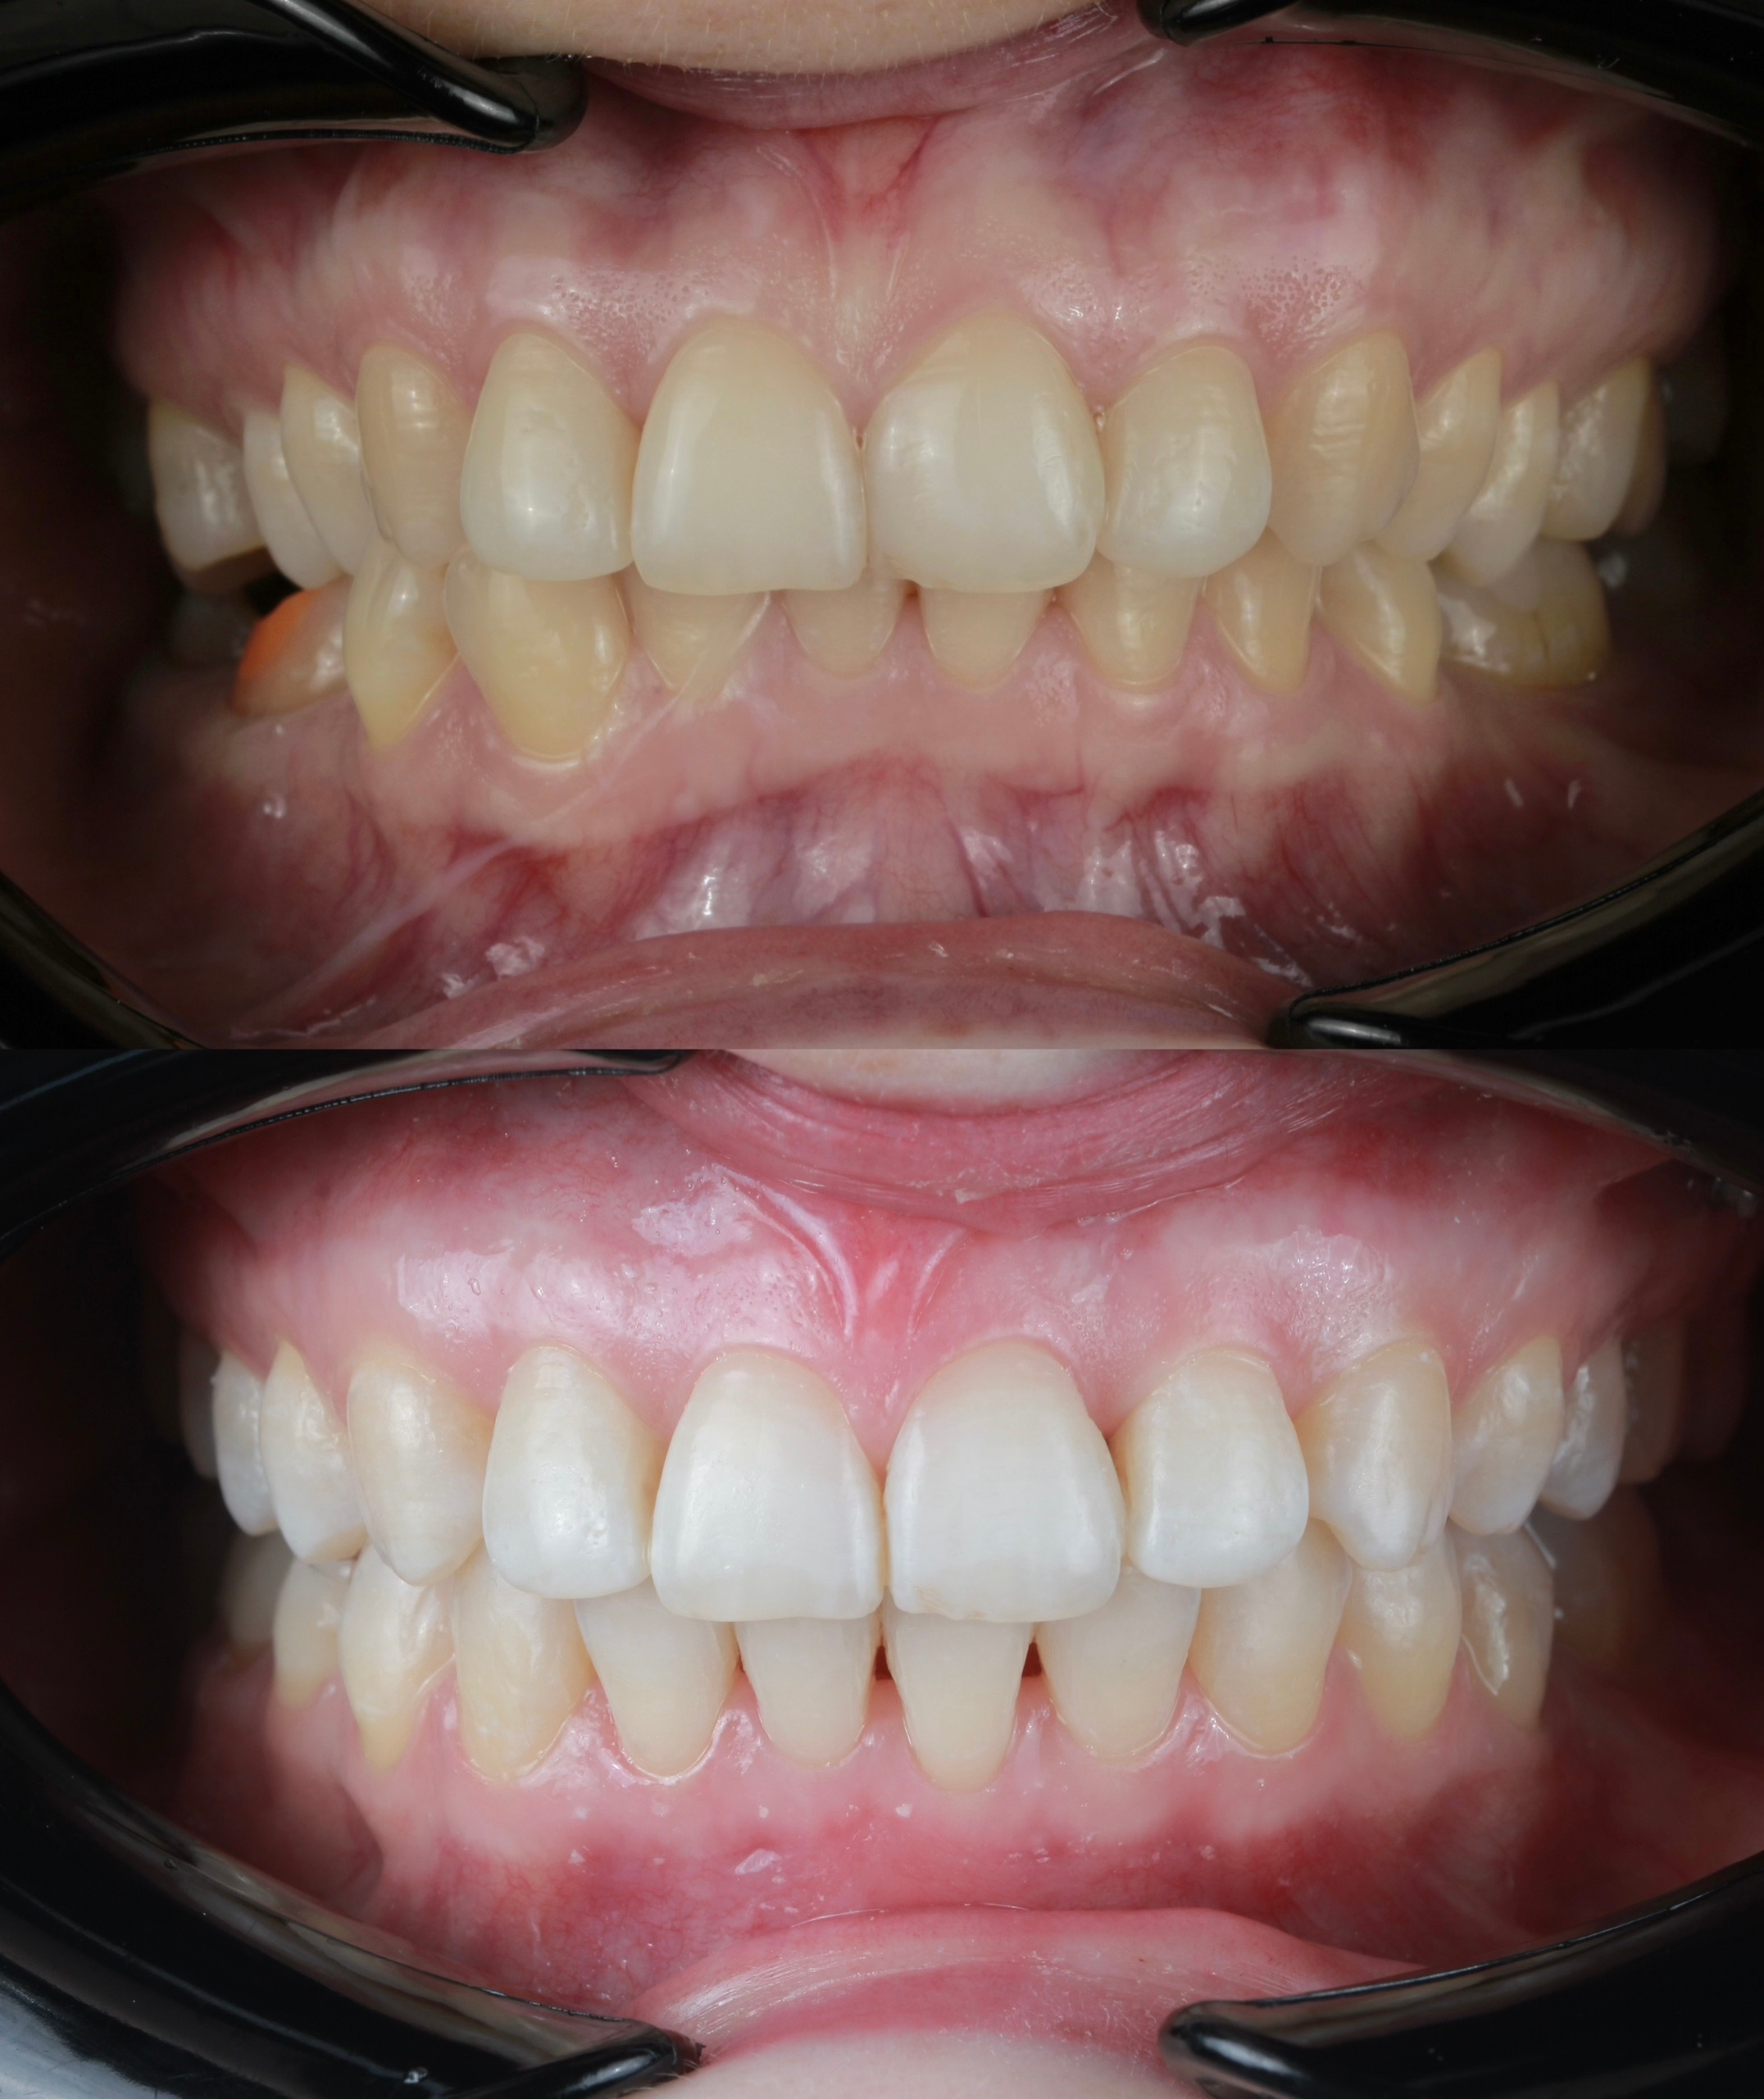

Клинический случай:

Рассмотрим пример ортодонтической коррекции на брекет-системе Damon Q. В данном случае срок лечения составил 1 год и 10 месяцев. За этот период удалось решить несколько важных задач:

• Устранение скученности зубов

• Коррекция наклона верхнего зубного ряда

• Удаление сильно разрушенного зуба на нижней челюсти и закрытие образовавшегося промежутка своими зубами

• Откорректированный прикус и центры зубных рядов

Работа была выполнена врачом-ортодонтом Глуховой Т.А., который тщательно подошел к каждому этапу лечения, чтобы достичь оптимального результата.